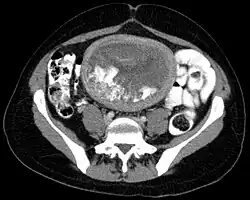

Die Blasenmole (Mola cystica) oder Traubenmole (Mola hydatidosa) ist eine Störung der Embryonalentwicklung in der Schwangerschaft. Durch eine Erweiterung der kleinen Plazentagefäße kommt es zu einer blasenartigen Umwandlung der Plazentazotten mit Einschmelzung des umgebenden Bindegewebes. Der Trophoblast zeigt eine gesteigerte Proliferationsaktivität.

Es wird zwischen teilweiser (90 %) und vollständiger (10 %) Blasenmole unterschieden. Die Übergänge zwischen der destruierenden (invasiven) Blasenmole und dem Chorionepitheliom sind fließend und in der Literatur nicht einheitlich. Begleitend zu einer Blasenmole treten bis kindskopfgroße Luteinzysten des Eierstocks auf, die sich infolge der hohen Sekretion von Gonadotropin (hCG) im Sinne eines Überstimulationssyndroms bilden.[1]

Anzeichen für eine Blasenmole können ein besonders schnell wachsender Uterus (Gebärmutter), ein hoch positiver Schwangerschaftstest, das Fehlen der fetalen Herztöne sowie besonders starke Schwangerschaftsübelkeit sein.

Die Diagnose wird über erhöhte Werte für das humane Choriongonadotropin (β-hCG) sowie über die Darstellung der verdickten Plazenta in Ultraschalluntersuchungen gestellt.